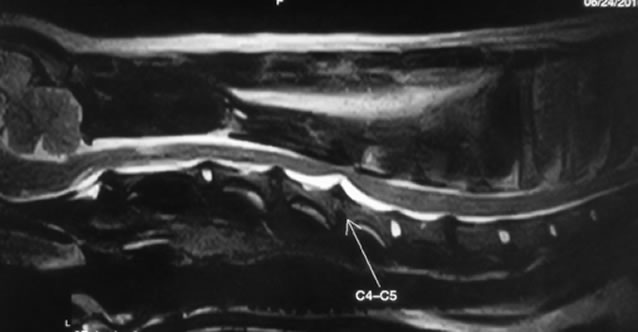

頸部椎間板ヘルニア

症状:何かの拍子にギャンギャン鳴く、頸部痛、四肢のふらつきや麻痺など

頸部椎間板ヘルニアとは

頸椎領域で椎間板の線維輪から脱出した椎間板物質等により、脊髄が圧迫されている状態です。痛みや神経症状をともないます。

好発犬種

ダックスが最も多い。他にビーグルなど。

診断

レントゲン検査、脊髄造影検査、CT検査、MRI検査

治療

Ventral Slotという頸椎の腹側に窓をつくり、脱出した椎間板物質を取り除き減圧する手術などを行います。